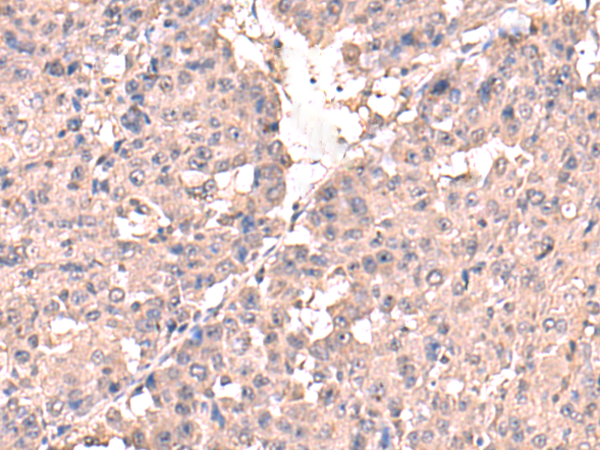

ELISA, IHC |

IHC positive control: |

Human liver cancer |

IHC Recommend dilution: |

50-300 |